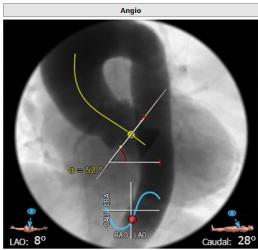

主动脉瓣Type 0型二叶瓣,瓣叶瓣缘结节样增厚伴中度钙化,开放受限。冠脉高度可。法式窦结构可,心脏角度约52°,左室较小,升主动脉未见明显扩张,右股动脉直径大于5.5mm,可作为主入路。患者为中度钙化的,重度主动脉瓣狭窄,呈鱼嘴型,结合主动脉根部结构,考虑植入Sapien 3瓣膜。

心脏角度